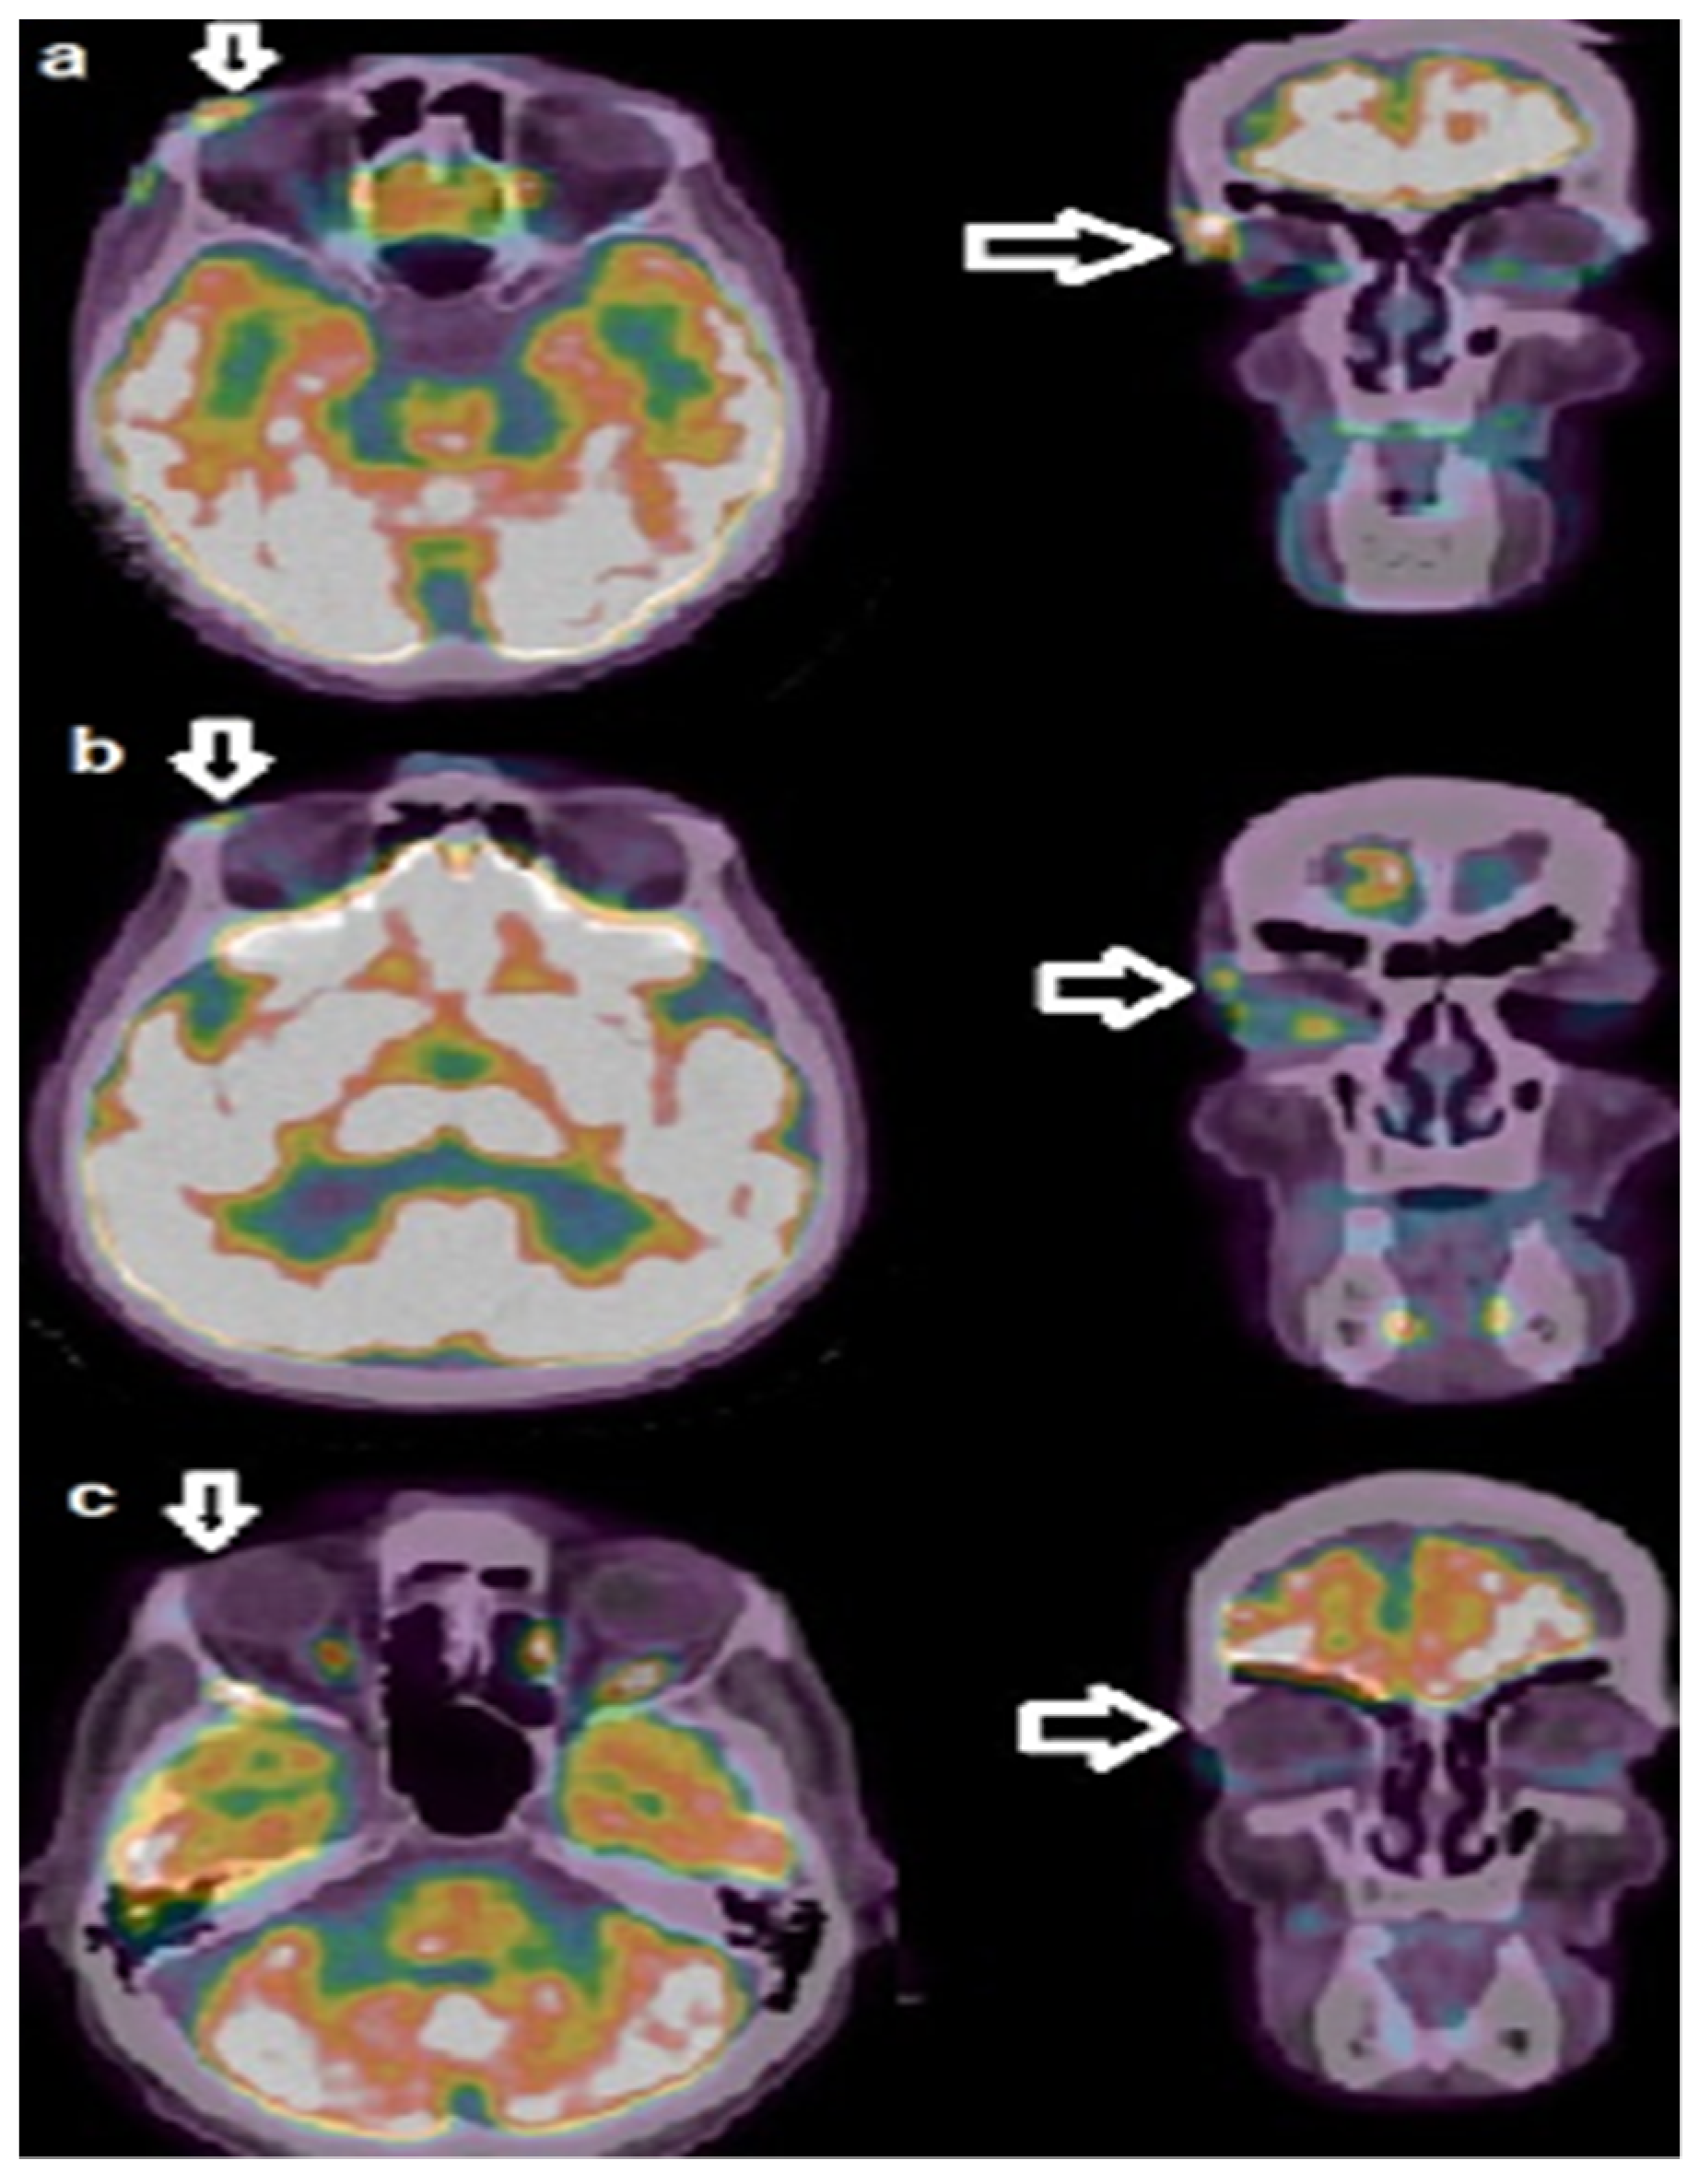

2. Detailed Case Description